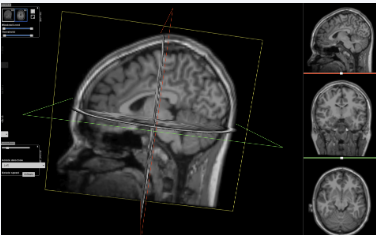

在计算机视觉领域,如果你想在 3D 医学影像(如 CT、MRI)中精准地“抠”出肿瘤或器官,传统的卷积神经网络(CNN)往往像是在“管中窥豹”——它擅长捕捉局部纹理,但容易忽略长距离的全局上下文。

本文将解析一项重磅研究:nnFormer(Volumetric Medical Image Segmentation Transformer)。它巧妙地将 Transformer 的全局建模能力与 nnU-Net 的自动化流水线结合,并在脑肿瘤、多器官及心脏诊断等多个核心任务上刷新了性能记录。